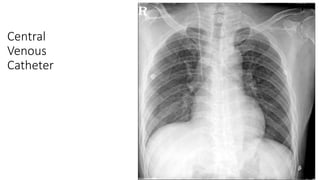

Central

Venous

Catheter

ICU – Tubesand Lines